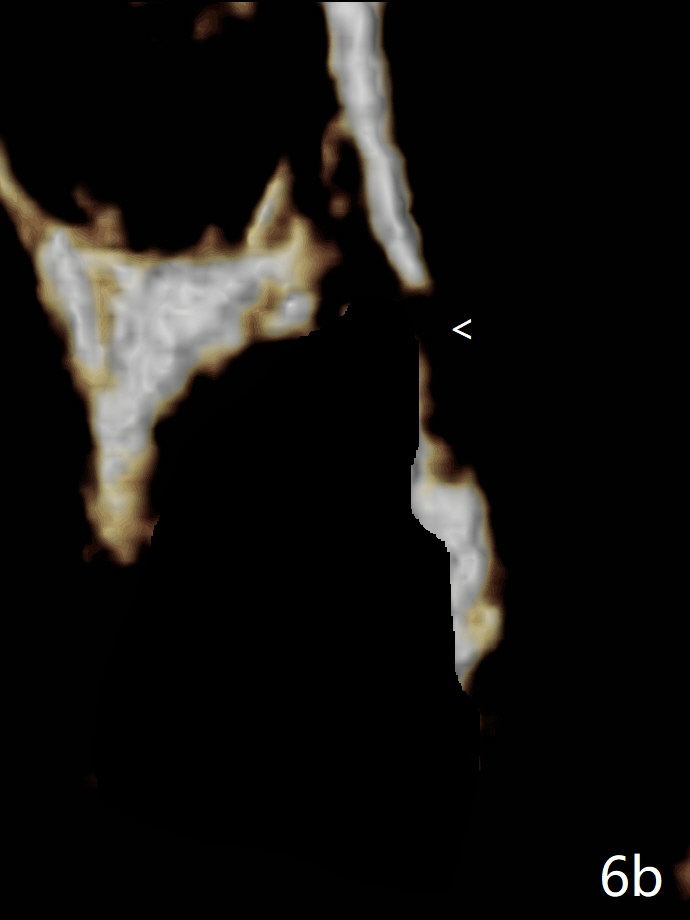

图六-a: 术前CT三维冠状切面显示左上5牙根(R);B: 颊侧。牙根拔除后(图六-b),根尖颊侧骨板缺失(<),